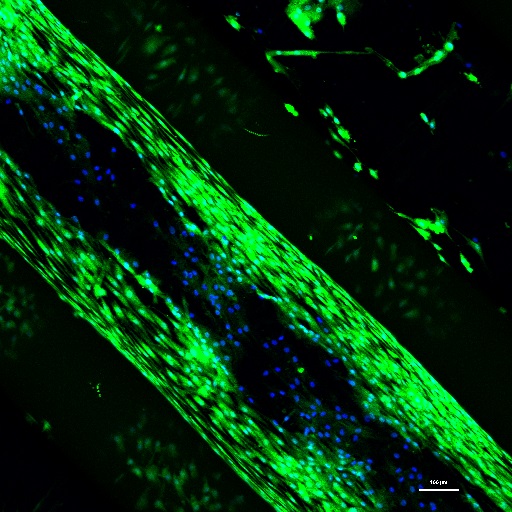

Un estudio revela cómo las células tumorales secuestran células sanas para promover la metástasis

21/02/2017